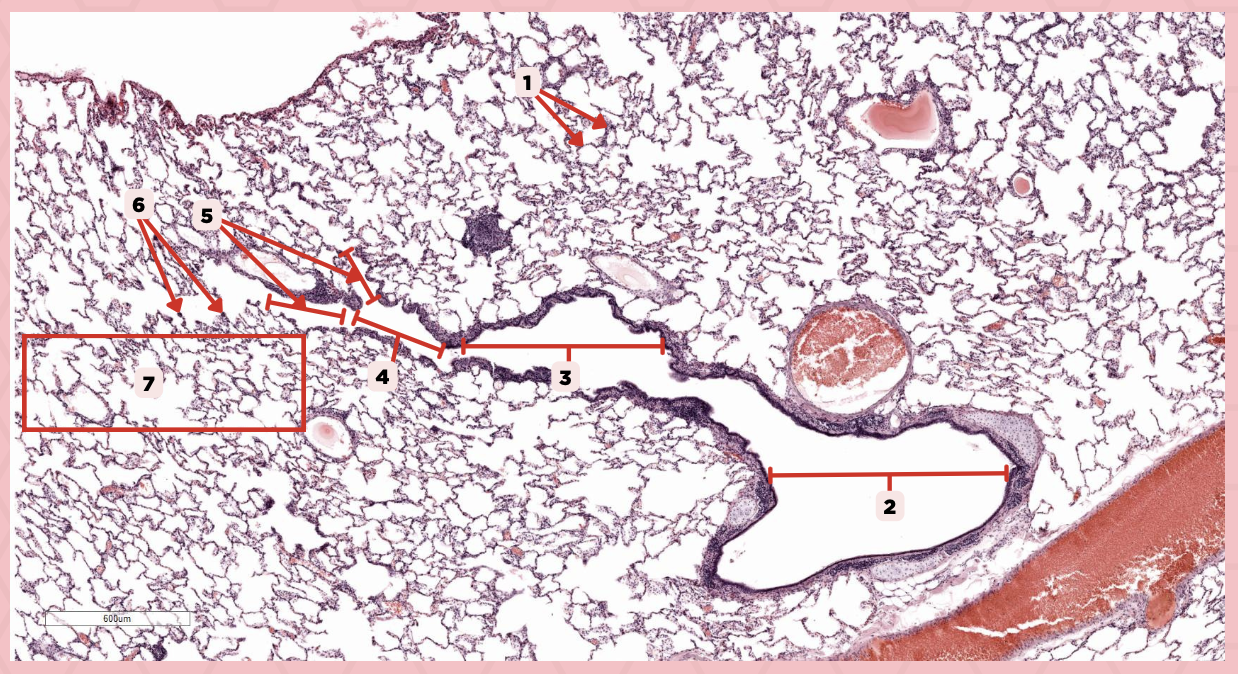

Lumens and Interalveolar septa

Name the irregular spaces and the fine threads of tissue that separate them.

Visceral pleura

Identify the structure labeled as 1.

Alveoli

Identify the structure labeled as 2.

Bigger and smaller intrapulmonary bronchi

What are the two types of intrapulmonary bronchi?

Pseudostratified epithelium (bigger bronchioles), Simple columnar or cuboidal (smaller)

What are the types of epithelium in No. 3?

Interalveolar septa

Identify the structure labeled as 1.

Intrapulmonary bronchi

Identify the structure labeled as 2.

Bronchiole

Identify the structure labeled as 3.

Terminal bronchiole

Identify the structure labeled as 4.

Respiratory bronchiole

Identify the structure labeled as 5.

Alveolar ducts

Identify the structure labeled as 6.

Alveolar sacs

Identify the structure labeled as 7.